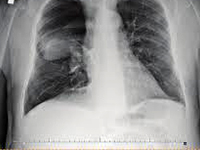

GinekologiaPrezentujemy przypadek 32-letniej pacjentki przyjętej do III Kliniki Chirurgii Ogólnej w Krakowie w celu przeprowadzenia tyroidektomii ze względu na raka brodawkowatego tarczycy. Pacjentka przeszła całkowitą tyreoidektomię z usunięciem węzłów chłonnych przedziału centralnego szyi bez żadnych komplikacji śródoperacyjnych. W pierwszej dobie po zabiegu zaobserwowano 300 ml mlecznego płynu w prawym drenie. Ze względu na utrzymujący się chłonkotok żywienie doustne zostało wstrzymane i rozpoczęto całkowite żywienie pozajelitowe. Objętości drenażu obserwowane w kolejnych dniach wahały się między 580 a 50 ml z tendencją malejącą. Dreny usunięto w 13 dobie po operacji bez śladu chłonkotoku.